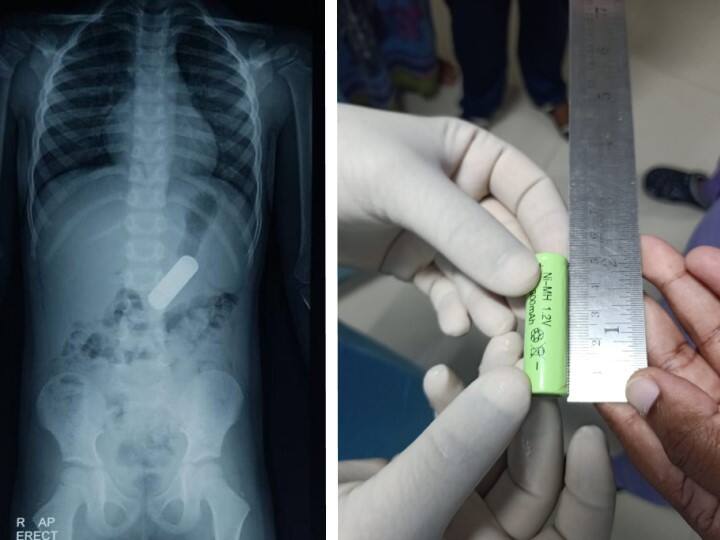

చిన్న పిల్లలు ఇంట్లో ఉన్నప్పుడు జాగ్రత్తగా ఉండాలి. వారి పరిసర ప్రాంతాల్లో చిన్ని చిన్ని వస్తువులు ఏవీ కనిపించకూడదు. వాటిని తినే వస్తువులు అనుకుని నోట్లో పెట్టేసుకుంటారు. చెన్నైకు చెందిన ఓ నాలుగేళ్ల ఇలాంటి ప్రమాదంలోనే చిక్కుకున్నాడు. రిమోట్తో ఆటలాడుతూ.. 5 సెంటీమీటర్ల పొడవున్న బ్యాటరీని తీసి నోట్లో పెట్టుకున్నాడు. అది అనుకోకుండా కడుపులోకి జారుకుంది. దీంతో పిల్లాడు ఏడ్వడం మొదలుపెట్టాడు. అదే సమయంలో అక్కడ ఉన్న అతడి తల్లిదండ్రులకు అనుమానం కలిగి వెంటనే హాస్పిటల్కు తీసుకెళ్లారు కాబట్టి సరిపోయింది. ఆ విషయం వారికి తెలిసి ఉండకపోతే.. బ్యాటరీలోని రసాయనాలు ఆ పిల్లాడి కడుపులోకి చేరేవి.

బాలుడికి ఎక్స్రే చేసిన వైద్యులు.. కడుపులో బ్యాటరీని కనుగొన్నారు. అయితే, దాన్ని సర్జరీతో మాత్రమే తొలగించాలని తొలుత భావించారు. అయితే, దాని వల్ల పిల్లాడు ఇబ్బంది పడతాడని భావించిన వైద్యులు.. ఎండోస్కోపీ విధానంలో బ్యాటరీని బయటకు తీయాలని నిర్ణయించుకున్నారు. అయితే, దాని వల్ల అవయవాలు దెబ్బతినే ప్రమాదం ఉందని వెనుకడుగు వేశారు. ఆలస్యం చేస్తే ప్రాణాలకు మరింత ప్రమాదమని భావించిన వైద్యులు చివరికి ఎండోస్కోపీ ద్వారానే బ్యాటరీ బయటకు తీయాలని నిర్ణయించుకున్నారు.

వైద్యులు ఆ బాలుడి నోటి నుంచి నెమ్మదిగా పైపును పంపి.. కడుపులో ఉన్న బ్యాటరీ వరకు చేరుకున్నారు. ఆ తర్వాత దాన్ని ఎంతో జాగ్రత్తగా, అతడి అంతర్గత అవయవాలకు గాయాలు కాకుండా బయటకు తెచ్చారు. ఇందుకు సుమారు 14 గంటలు శ్రమించారు. బ్యాటరీలోని రసాయానాలు లీకయ్యే లోపే.. దాన్ని బయటకు తీసేసి పసివాడి ప్రాణాలు కాపాడారు.

ఈ చికిత్సను రేలా హాస్పిటల్లో నిర్వహించారు. సీనియర్ గ్యాస్ట్రోఎంటరాలజిస్ట్ డాక్టర్ ఆర్.రవి మీడియాతో మాట్లాడుతూ.. ‘‘దాదాపు 14 గంటలు శ్రమించి ఎంతో జాగ్రత్తగా ఆ బ్యాటరీని బయటకు తీశాం. పిల్లలు మనకు తెలియకుండానే బటన్లు, నాణేలు, బ్యాటరీలు తదితర చిన్న చిన్న వస్తువులను మింగేస్తారు. కాబట్టి జాగ్రత్తగా ఉండాలి. వాటిని మలంతోపాటు బయటకు రావు. కడుపులోనే ఉండిపోతాయి. కడుపు నుంచి కొన్ని యాసిడ్లు విడుదలవుతాయి. దాని వల్ల బ్యాటరీ తుప్పు పడుతుంది. ఆ తర్వాత అందులోని రసాయనాలను కడుపులోకి వదులుతుంది. అది విషపూరితమై ప్రాణాలకు ప్రమాదకరం కావచ్చు’’ అని తెలిపారు.

#Chennai - without surgery, doctors save 4yr old who ingested 5cm-long AA battery, which ws nearly the size of his food pipe

Batt was lodged in stomach, had risk of corroding in contact with acid

Rela hospital Docs performed endoscopy with a 'Roth net' & removed foreign object pic.twitter.com/jmsnfXwUgH